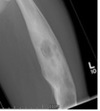

What may plain x-ray show in osteomyelitis? (x3)

- ACUTE: osteopenia after week of disease onset, evidence of bone destruction, periosteal reaction

- CHRONIC: intermedullary (resorption of inner layer of cortex), cavities and ‘fallen leaf’ sign when a piece of endosteal sequestrum has detached and fallen into the medullary canal (shown in image)